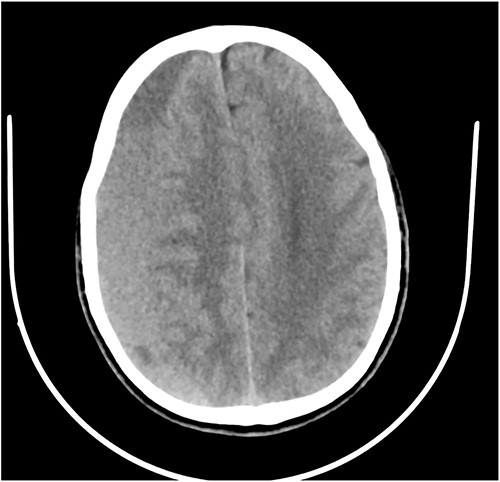

Case 3 – left isolated foot drop

A 78-year-old man with a 1-week history of headaches and dragging of the left foot. He had fallen in the bathroom 6 weeks prior to presentation. He had no other symptoms. Examination was unremarkable except for a left-sided foot drop with increased ankle jerk reflex. Brain CT done revealed a right-sided fronto-parieto-temporal CSDH (Figs 3 and 4). He had burr hole drainage and was discharged 3 days later to continue physiotherapy at home. At 4 weeks follow-up, his symptoms had completely resolved.

While few reports of bilateral lower extremity weakness have been reported with CSDH, unilateral foot drop is extremely rare. Two previous cases of isolated foot drop from CSDH have been reported, Sengupta et al. [17] and Weisberg [18]. Direct cortical compression of the motor foot area of the homunculus against the falx cerebri is the likely explanation in this scenario given the large right hemispheric CSDH. While the clinical suspicion of an intracranial lesion was considered due to raised ankle reflex, a diagnosis of CSDH before imaging was not entertained because of the rarity of isolated foot weakness.